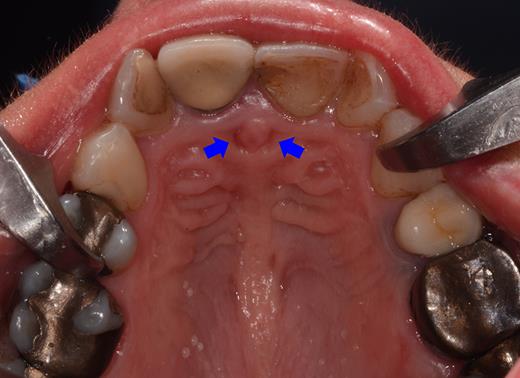

Clinical examination revealed two small mucosal openings on either side of the incisive papilla, which could be probed partially (Fig. 1). Palpation of this area was painful. Two gutta-percha points were inserted into the two openings (Fig. 2). The cone beam computed tomography (CT) confirmed two patent NDPs with oronasal communication (Fig. 3).

Preoperative clinical situation: occlusal view of the maxillary arch presenting two small depressions of the mucosa on either side of the incisive papilla (blue arrows).